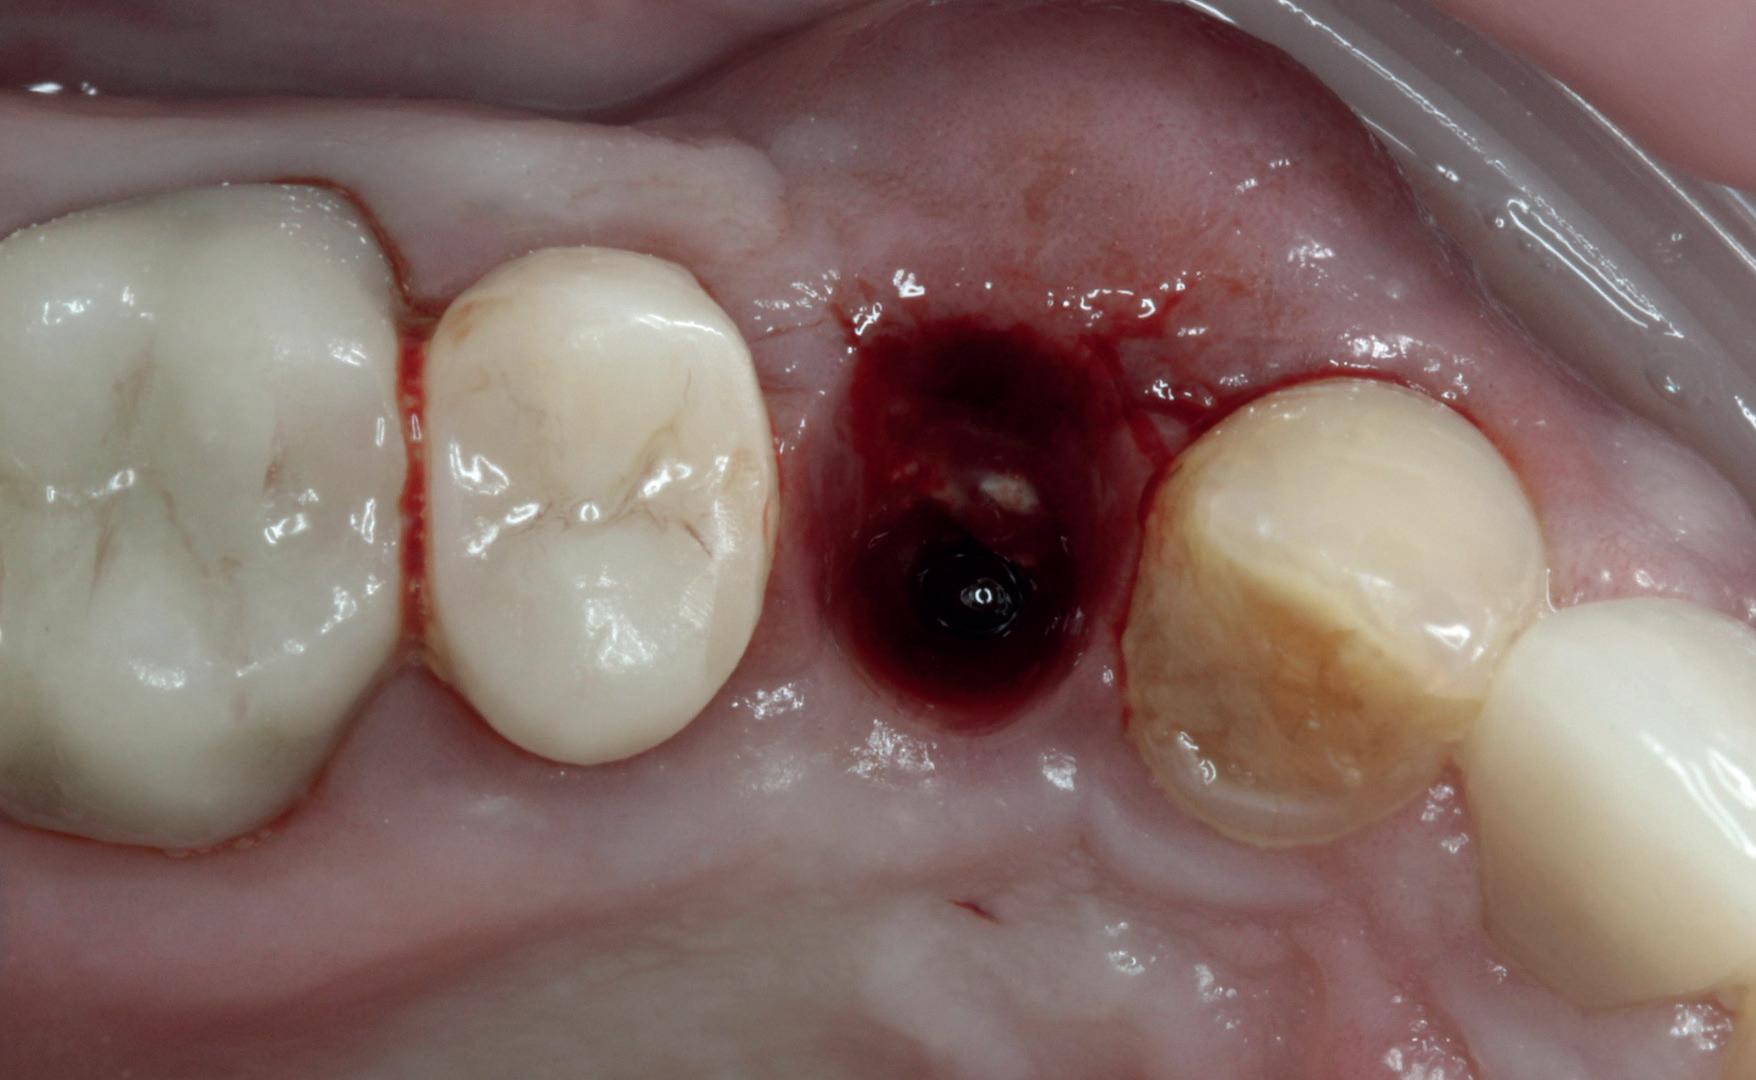

1. Afgebroken 24. Geen hoektandgeleiding aanwezig.

2. Decapiteren van het element en splitsen van de wortels.

3. Verwijderen van de radices.

4. Curettage en spoelen met een zoutoplossing.

5. Het ridge preservation protocol waarbij we proberen zoveel moge-

lijk bot te behouden met behulp van een xenograft.

6. De tijdelijke pontic, waarbij gebruikgemaakt wordt van de eigen afgebroken kroon en wat composiet. 7-10. Een full thickness flap osteotomie met hand plaatsing van een MegaGen AnyRidge Implantaat volgens protocol resulteerde in een

De implantaatplaatsing en de beslissende fout (afbeelding 1-13)

De extractie verliep voorspoedig, waarbij ik zoals al-

primaire stabiliteit van 60 Ncm.

11. Röntgenfoto ter controle van de plaatsing en de angulaire. Dit bone-level implantaat werd 4 mm onder de weke delen geplaatst.

12. Direct post-op. Een direct geplaatste tijdelijke kroon. Vastgezet met een torque van 20 Ncm en gehecht met prolene 5/0.

tijd probeerde de buccale botlamel intact te houden. Dit is cruciaal voor latere botbehoud en implantaatplaatsing. Na curettage en spoelen van de alveole beoordeelde ik de situatie opnieuw: de botcondities leken gunstig voor een immediaat implantaat.

Hier begon echter de cruciale fout in mijn klinisch besluitvormingsproces. In mijn streven naar maximale primaire stabiliteit - wetende dat immediaat belasten enkel mogelijk is bij hoge stabiliteit -on-

13. Röntgenfoto ter controle van de pasvorm van de direct geplaatste tijdelijke kroon.

derprepareerde ik de osteotomie. Dit betekende dat ik een iets te smal implantaatbed creëerde, in de hoop dat het implantaat stevig in het bot verankerd zou worden.

Op papier leek dit een logische stap: het MegaGen AnyRidge-implantaat dat ik koos, gaf me een stabiliteit van 60Ncm—een cijfer dat vertrouwen gaf in immediaat belasten. Maar in mijn enthousiasme had ik onvoldoende rekening gehouden met de biologische gevolgen van overmatige compressie.

Door de te hoge druk op het omringende bot verminderde daarin de doorbloeding, wat leidde tot een verhoogd risico op botnecrose. Dit was geen fout van abutmentkeuze of occlusie; dit was puur het gevolg van mijn drang naar optimale stabiliteit en de wens om het implantaat direct te belasten, onder invloed van patiëntdruk.